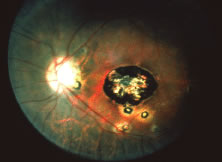

The ARN patient typically presents with progressive visual blurring in one or both eyes occurring over several weeks. These patients often are initially treated with corticosteroids, antitoxoplasmosis drugs, and other medications before arriving at the correct diagnosis. Examination reveals a prominent anterior uveitis that may be granulomatous or nongranulomatous (Fig. 1). Inflammatory signs may be prominent and cause severe pain (Fig. 2). The uveitis may be diffuse and so severe that it causes proptosis. These signs, and the diffuse vitreitis that makes the view of the retina difficult, may contribute to the high degree of delayed and/or misdiagnosis that occurs in the early stages of the disease. Significant vitreous cellular infiltration is seen in the presence of retinitis that is manifest by opacification of the retina, often most prominently in the periphery. Posterior pole involvement may include retinitis, as well as inflammation of the optic nerve head. Optic neuropathy might be the first sign of ARN with subsequent development of other retinal manifestations.8 Ultrasonography and computed tomography (CT) might be helpful in cases of ARN associated with optic nerve edema revealing enlargement of the optic nerve sheath.9 Even in ARN patients who are not immunocompromised and who have no clinical evidence of encephalitis, magnetic resonance imaging of selected cases has shown lesions of the lateral geniculate, optic tracts, and chiasma, which suggests that the virus spreads through the central nervous system (CNS) by axoplasmic transport from the retinal ganglion cells.10 A secondary retinal vasculitis is common, often accompanied by a mild number of retinal hemorrhages. Days to weeks after onset of the infection, the discrete peripheral lesions typically coalesce into a white or yellow ring of infected retina, and the associated vasculature is obliterated (Fig. 3). Necrotic retina desquamates into the vitreous resulting in vitreous sheets.3,6 Eventually, most untreated eyes can be expected to develop retinal detachment resulting from development of multiple full-thickness retinal breaks accompanied by traction or exudation.11 Giant retinal pigment epithelial tears have also been reported.12

Fig. 3. Confluent peripheral retinitis seen in acute retinal necrosis. The perivascular lucent areas with some evidence of hemorrhage are typical of this disease.

A variable number of eyes, up to 75%, develop retinal detachments (Fig. 5). Prophylactic laser for demarcating the areas of active retinitis from normal retina has been advocated to create chorioretinal adhesions that prevent retinal detachments around sites of retinal break formation (which usually occur at the zone between affected and healthy retina). Han and associates43 reported five cases treated with prophylactic laserpexy in addition to antiviral, steroid, and antiplatelet therapy. After 15 months of follow-up, no retinal detachments were noted. Sternberg and coworkers44 described a 75% decrease in the rate of retinal detachment using prophylactic photocoagulation. Some have advocated the creation of a “new ora serrata” by applying confluent rows of laser burns posterior to the areas of retinitis. However, if traction forces from vitreous organization, epiretinal membrane (ERM) formation, or proliferative vitreoretinopathy develop as they commonly do, the contractile forces will be able to overcome any increased chorioretinal adhesion created by the laserpexy. However, McDonald and associates45 reported failure of prophylactic peripheral laserpexy to prevent retinal detachment in ARN patients. In addition, many cases of ARN result in a severe vitritis, limiting the view for a planned laserpexy (Fig. 6). Therefore, vitrectomy with endolaser and concomitant encircling of the eye with a scleral buckle to reduce traction may be required in some patients.46,47 Decisions relating to the need for scleral buckling to support retinal breaks and the use of silicone oil or long-acting gases to repair retinal detachments should be made by an experienced vitreoretinal surgeon.40,48 Selection of cases to undergo operation should be made with consideration given to optic nerve function, visual potential, and medical control of retinitis.

Fig. 5. A patient with funnel-shaped retinal detachment and proliferative vitreoretinopathy complicating acute retinal necrosis syndrome.